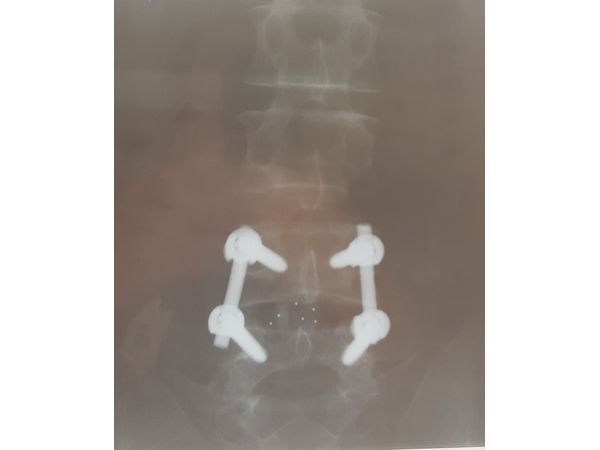

⠀•⠀микродискэктомия (удаление межпозвонковой грыжи) с последующим спондилодезом (обездвиживанием позвонков) PLIF кейджами Peek CONCORD Вullet и фиксацией сегмента 4 винтовой ТПФС фирмы Stryker ХIA3.

2. Под контролем электронно-оптического преобразователя (в двух проекциях) в ножки L4 и L5 позвонков установлены полиаксиальные винты длиной 55 мм и диаметром 6,5 мм.

3. В предварительно ревизованный межпозвонковый диск L4-L5 с обеих сторон после очищения замыкательных пластин смежных позвонков установлены два кейджа типа Peek CONCORD Bullet размерами 9*11*27 мм. Полость кейджей заполнена аутокостью. Винты стоят адекватно, укреплены на стержнях.